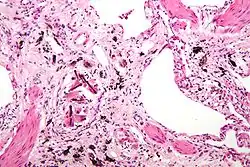

| Micrograph of asbestosis (with ferruginous bodies), a type of pneumoconiosis. H&E stain. | |